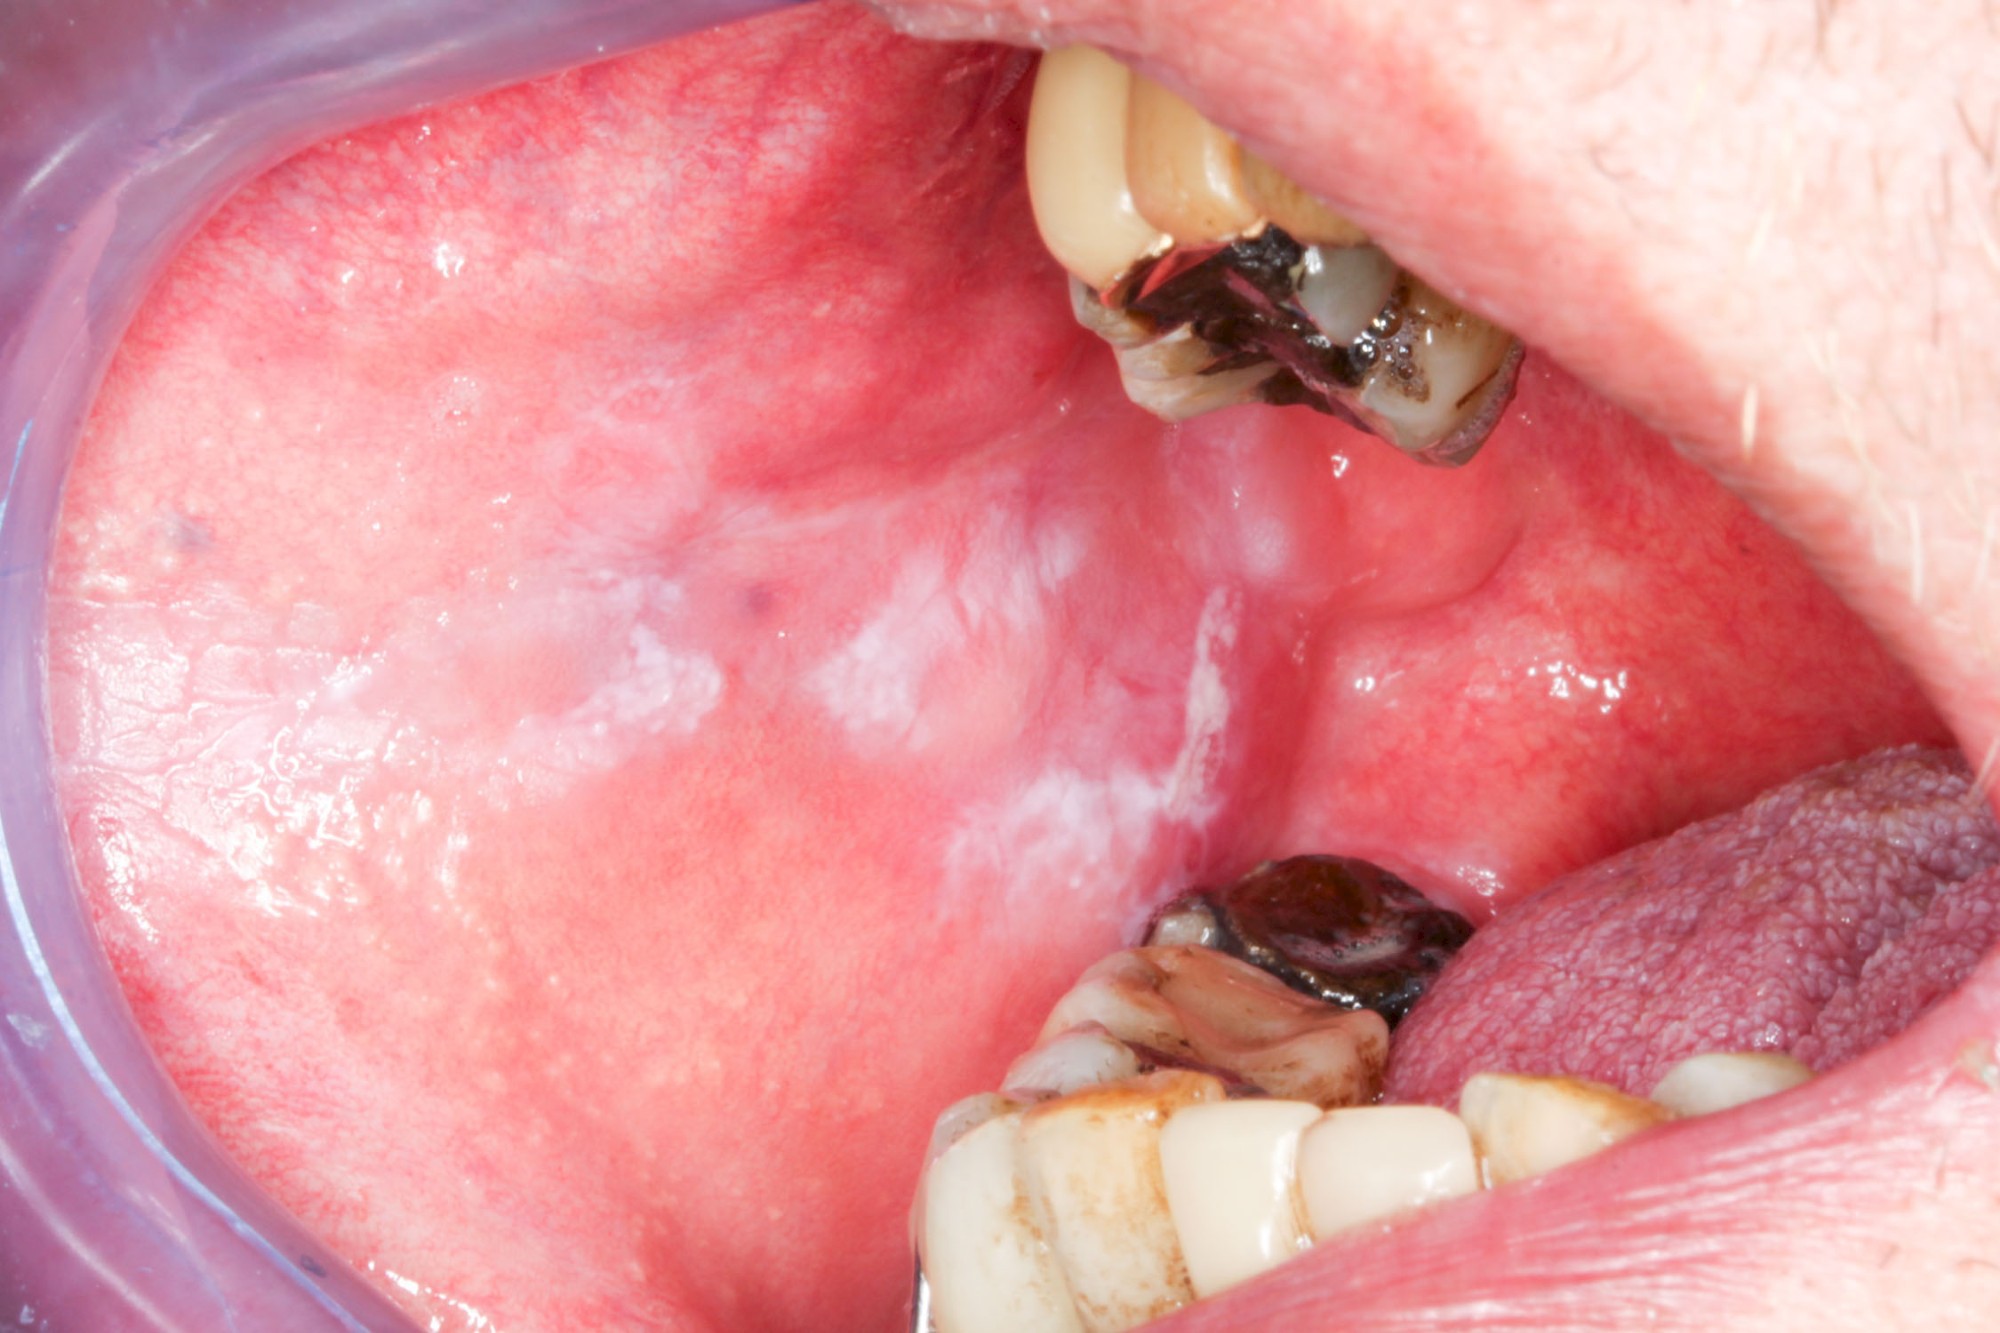

Leukoplakie, Erythroplakie

Die Auffälligkeiten sind zurückzuführen auf gestörte bzw. überschießende, z. T. entzündliche Stoffwechselvorgänge im Bereich der Schleimhäute.

Bei der sogenannten Leukoplakie handelt es sich um eine Hyperkeratose (Hornhautbildung), die auch entarten kann (fakultative Präkanzerose).

Nach dem Erscheinungsbild werden verschiede Typen unterschieden:

- Plan (Leukoplakia simplex bzw. plana): homogen-weiß, meist klar begrenzt, Oberfläche glatt. Entartungsrisiko 0–3 %

- Warzenartig (Leukoplakia verrucosa): homogen-weiß, meist klar begrenzt, Oberfläche warzig. Entartungsrisiko 11–20 %

- Erosiv (Leukoplakia erosiva): inhomogen weiß mit roten Anteilen. Entartungsrisiko ca. 30–38 %

Demgegenüber hat die Erythroplakie als homogen-rötliche Erscheinung (häufig mit einem weißlichen Anteil im Randbereich) ein deutlich erhöhtes Entartungsrisiko, weshalb man hier auch von einer obligaten Präkanzerose beziehungsweise einem Carcinoma In Situ (CIS) mit invasivem Wachstum ausgeht – vor allem, wenn die Veränderung am Mundboden, am Zungenrand oder an der Zungenunterseite lokalisiert ist.

Neben mechanischen Reizen zählen auch Rauchen und Alkoholkonsum zu den möglichen Ursachen. Manchmal sind diese Veränderungen, etwa wenn die Auffälligkeit im Bereich der Wange oder auch der Zunge auf Höhe der Zahnreihe im Zubiss (Okklusionsebene) zu liegen kommt, auch auf Wangen- bzw. Zungenkauen als Ursache zurückzuführen. Die beobachtbaren Veränderungen reichen hier von diskreten homogen-weißlichen Strichen (Linea alba) bis hin zu erosiv "unruhigen" Schleimhautarealen. Je nachdem, wie intensiv und wie ausdauernd und mit welcher Kraft diese Habits ausgeführt werden. Auch hier sollte auf eine Verhaltensänderung hingewirkt und ein Zahnarzt verständigt werden.